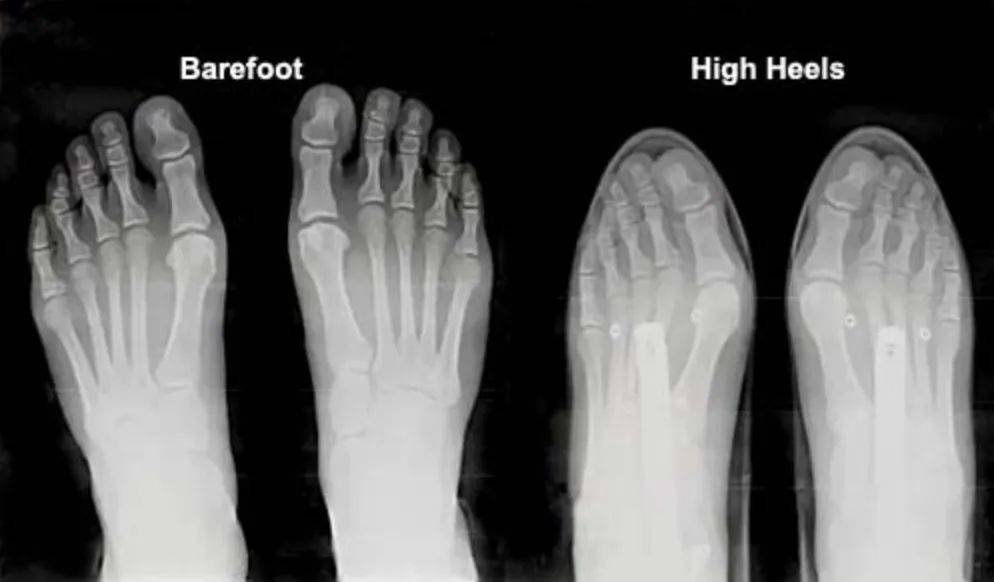

反观在现代社会,高跟鞋、尖头鞋、强支撑鞋的出现正在重塑人们的足部。而其带来的可能是更多的损伤,比如说尖头高跟鞋兴起后而导致的拇指外翻,缓冲跑鞋的出现反而造成了更多的下肢损伤。

赤足与高跟鞋对比